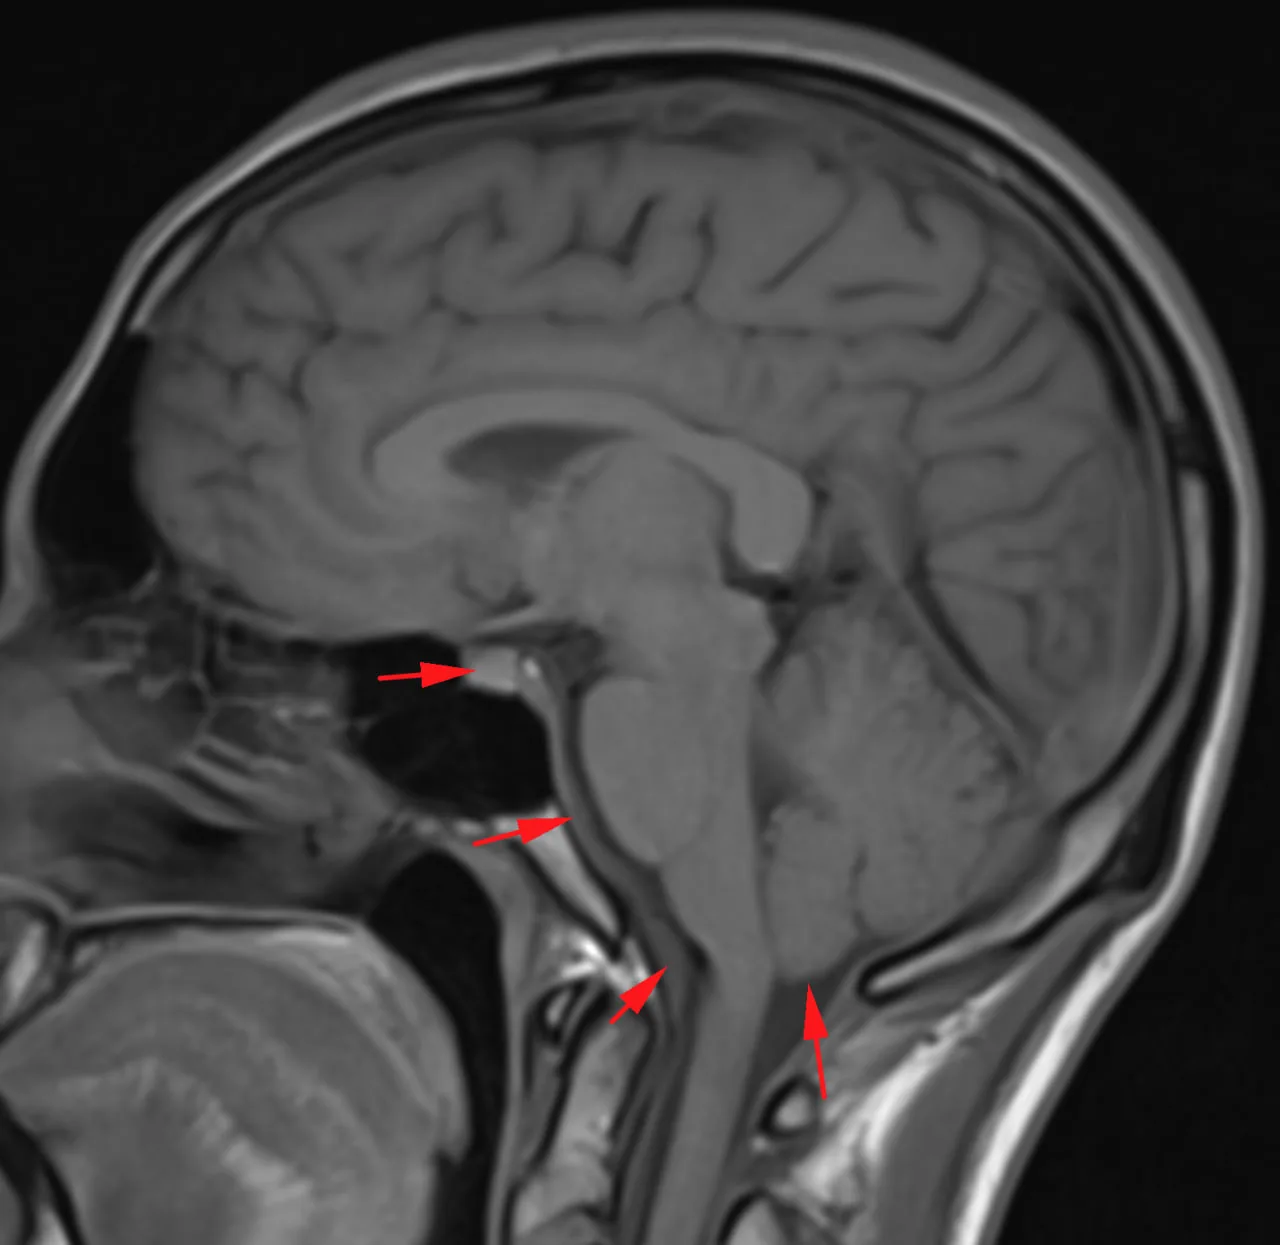

Наконец-то я увидел это воочию! Киста полости Верги, промежуточного паруса, осложнённая гидроцефалией. Из анамнеза: Низкое артериальнео давление, нарушение речи, затуманенное сознание, головная боль, головокружение, в 1989 году перенёс менингит.

А Вы видали такое? Я впервые вижу, раньше только читал в литературе.

Внутричерепная гипотензия из чата: СКУДО (Субдуральная гигрома (здесь нет, но есть Контрастирование облочек), Утолщение твёрдой мозговой оболочки, Длинный гипофиза, Опущенный мозг).

Кроме того, есть узкие желудочки и толстые раздутые синусы ТМО.